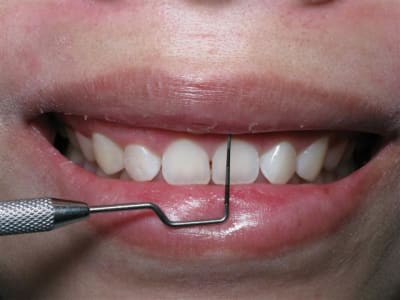

Il y a plusieurs trucs que je ne comprends pas dans ce raisonnement, si tu ne fais pas une incision intra-sulculaire c'est pour ne pas avoir de récession surtout sur ta ccm.

Hors, tu as un cas qui ne demande que ça. En effet il semble que les dents soient légèrement "impactées" et le ratio longueur/largeur est inesthétique, surtout avec un sourire gingivale.

Petite question pour le cas de Ceramik justement:

pourquoi pas de d'allongement de couronne dans ton cas qui présente les mêmes caractéristiques: émail recouvert ( après ortho peut-être) et gummy smile ?

Qui te dit que ça n'a pas été fait après ?

Une combinaison de techniques était nécessaire dans ce cas.

Non seulement un ''lip-tack''

pas de travail osseux.